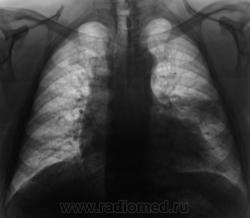

2. Конечно, мы на свой страх и риск, произвели дообследование, согласно стандарту. Итог дообследования представлен в серии 3.

Все признаки периферического рака...."расти" так может и лет пять...пока репу в диспансере будут чесать...

В заключении, именно однозначно, выставлен данный диагноз, изображения и все необходимое записано на диск. Это не ошибка для ООД. В ООД такой ошибки быть не может, ибо это специализированное учреждение.  Кстати, это, как Вы понимаете, случай не единичный.